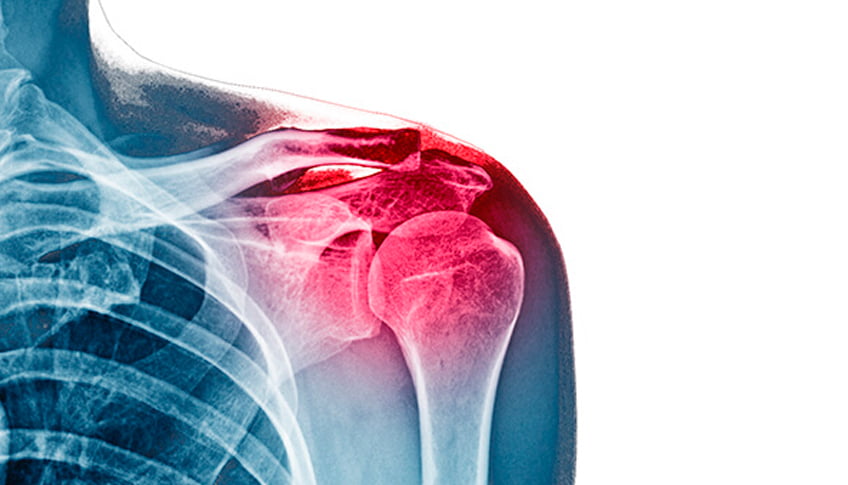

Артроскопія плечового суглоба: основні принципи, діагностика патологій, вивихи та операційні заходи.